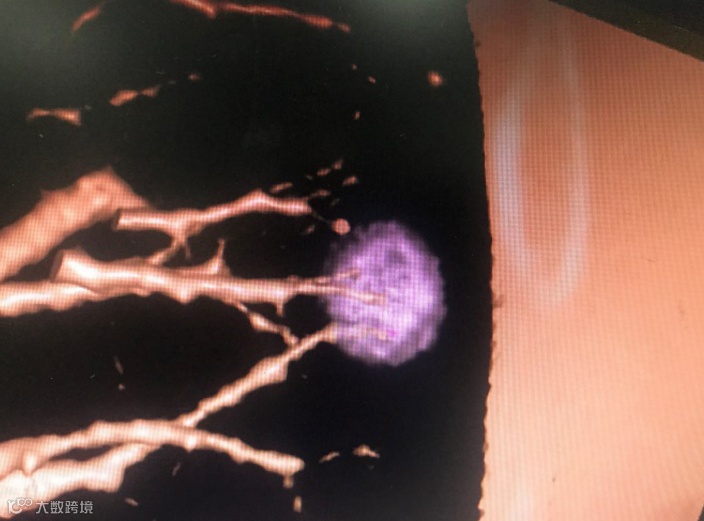

如病情需要,临床医生们会建议进行CT影像后处理,即当前比较流行的肺小结节三维重建技术。

我有两种不同的磨玻璃形态:pGGN (单纯性毛玻璃结节)和mGGN (混合性毛玻璃结节)。具体如图: